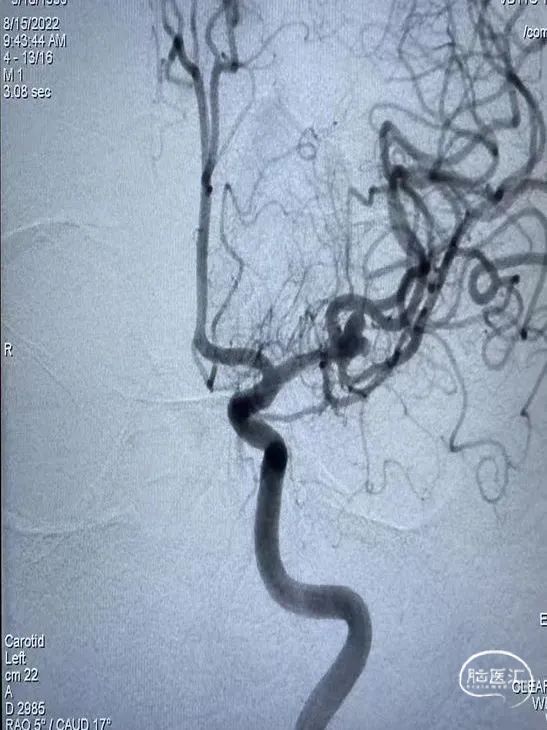

左侧大脑中动脉动脉瘤

动脉瘤部位:

动脉瘤尺寸:

动脉瘤测量:

动脉瘤特点:

手术策略:支架辅助弹簧圈栓塞

术前影像